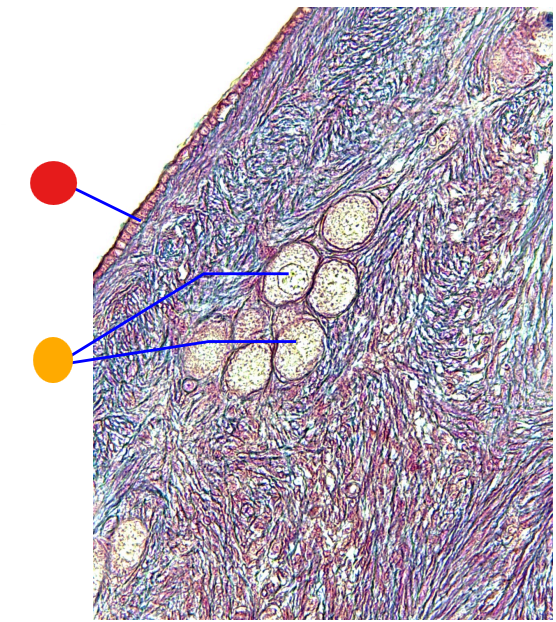

red

primordial follicles

red

primary follicles

red

tunica albuginea

orange

primary oocyte

yellow

primordial follicles

red

tunica albuginea

orange

primordial follicles

red

primary follicle

orange

secondary follicles